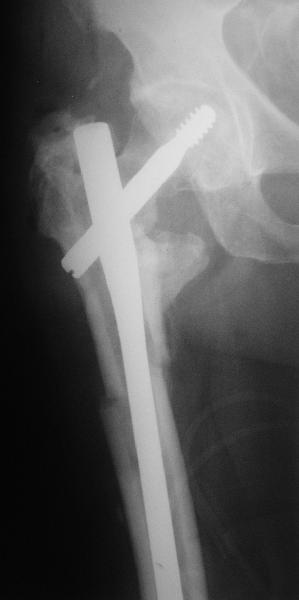

На прошлой неделе оперировали похожего пациента. 2 года после неудачного остеосинтеза PFN в другом регионе. После удаления остатков железа выявилось несращение вертельной области.

В такой ситуации важно устранить варусную деформацию. При использовании гвоздя это непросто. Поэтому в число рассматриваемых

вариантов стоило бы включить вальгизирующую остеотомию с фиксацией 130-градусной клинковой пластиной или DHS.

Если есть сильное желание фиксировать все-таки гвоздем, советовал бы ввести мощный "джойстик" параллельно оси шейки бедра близко к ее задней стенке, сделать поперечную межвертельную остеотомию и использовать дистрактор таз-бедро.

Поскольку в нашем случае выявилась подвижность, мы наложили дистрактор таз-бедро на 3 дня, и сделали остеосинтез гаммой без остеотомии. То, что произошла "корригирующая остеоклазия" в подвертельной области, выявили после введения гвоздя. Пациент уже уехал домой, будем наблюдать.